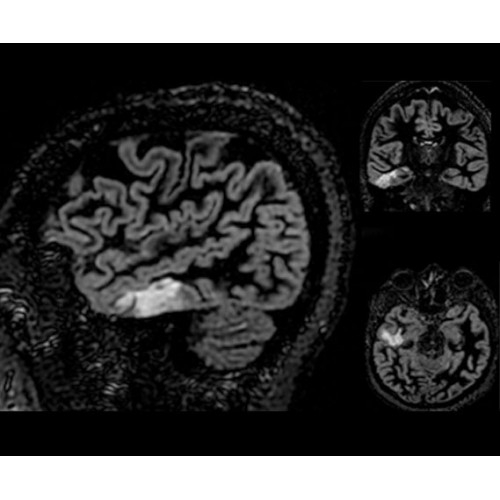

SIGNA PET/MR 3.0T — это гибридная система, в которой совмещаются две принципиально разные технологии — магнитно-резонансную томографию (МРТ) и позитронно-эмиссионную томографию (ПЭТ). Система отличающийся высокой чувствительностью и эффективностью и предназначена для диагностики в области онкологии, неврологии, кардио-васкулярных исследований, исследований воспалительных процессов.

Компания GE Healthcare представляет революционную, полностью интегрированную систему SIGNA PET/MR1, в которой сочетаются времяпролетная технология (TOF) и возможности напряженности магнитного поля 3.0 Тл. Мы поможем вам поднять исследования на более высокий уровень. SIGNA PET/MR позволяет достичь впечатляющей точности и скорости исследований, а благодаря новейшей технологии реконструкции Q.Clear2 качество изображений улучшается в два раза. Кроме того, в систему включен полный набор клинических приложений и гибких катушек для проведения любых видов исследования, открывая для вас возможности визуализации, о которых вы даже не догадывались.

• Специальный пакет приложений для измерения и сравнения объемных изображений ЦНС с нормами поможет вам в диагностике нейродегенеративных заболеваний, а дополнительные инструменты визуализации — в постановке точного диагноза с помощью бета-амилоидов и радиоизотопных маркеров ФДГ.